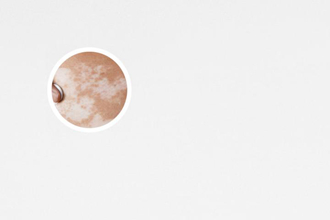

白癜風(fēng),其醫(yī)學(xué)特征為皮膚上出現(xiàn)不同大小的白斑。在治療白癜風(fēng)的過程中,有時(shí)會(huì)出現(xiàn)白癜風(fēng)邊緣不清晰的情況,給患者帶來困擾。本文將從多個(gè)角度討論白癜風(fēng)治療中邊緣不清晰的問題,幫助患者更好地理解和處理這一情況。

白癜風(fēng)邊緣不清晰的出現(xiàn)可能與多種因素有關(guān)。白癜風(fēng)的病因尚不明確,目前認(rèn)為可能與遺傳、免疫系統(tǒng)異常、自身免疫等因素有關(guān)。白斑邊緣的不清晰可能與治療方式、患者個(gè)體差異等方面有關(guān)。治療白癜風(fēng)邊緣不清晰需要綜合考慮多種因素。